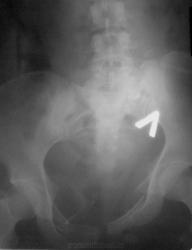

Случай 2.

Мужчина. ДТП, этим все сказано....ну и - всего много...

2. Оскольчатая бабочка + разрыв симфиза. С левой подвздошной в крыле - не совсем уверена. Удивительно, что мочевой цел... или ошибаюсь?

2. И крыло подвздошной, и левая половина крестца, и поперечный пятого поясничного - все так и есть... Да, на удивление, мочевой "удержал")))

А по крестцу - каша, не понять... Поперечный 4-го отлетел слева, а в поперечном 5-м видится асимметричная сакрализация. Крыло погнуто наверняка, но деталей не могу рассмотреть, наощупь всё). Мочевой - молодец, железный мочевой)).

А во втором случае - таз всмятку!

Случай №2. Перелом крестцовоподвздошного сочленения слева со смещением подвздошной кости. Двусторонний перелом лонных и седалищных костей, разрыв лонного сочленения.